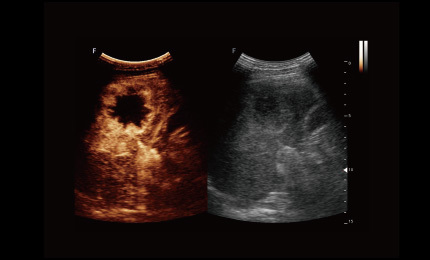

obrazowanie kontrastowe

Zaawansowane obrazowanie kontrastowe umożliwia dokładniejsze uwidocznienie struktur poprzez wykorzystanie sygnałów pochodzących z mikropęcherzyków kontrastowych. Pozwala to na uzyskanie wysokiego kontrastu obrazu i bardziej szczegółową ocenę zmian.